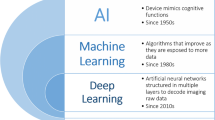

Artificial Intelligence applications have recently demonstrated high diagnostic accuracy and increased workflow efficiency in radiology. Machine learning models, particularly deep learning, can perform complex tasks in medical imaging, especially when they are trained with a large amount of high-quality data. For effective realization of the potential of artificial intelligence in interventional radiology, some unique challenges involving data storage, interoperability, adoption of standards, and conflict of interest between physicians and developers need to be addressed. With immense innovation and technological breakthrough, the scope of interventional radiology is continuously increasing in both width and breadth, and so are the opportunities of AI to revolutionize the sector. Artificial intelligence can complement the efforts of the interventional radiologist through decision support, triaging and screening of patients, prevention of error, procedural and periprocedural support, patient monitoring, prognostication of diseases, outcome prediction, image acquisition, image processing, etc. In conjunction with augmented reality systems, it can also help in improving procedural skills of interventional radiology residents and fellows through superior simulation training. Artificial intelligence has a tremendous potential to boost the productivity of radiologists. However, they are unlikely to replace them as there are significant apprehensions regarding the legal accountability, transparency, fairness, equality, bias, or potential misuse by an artificial intelligence system which prevent any independent action or clinical application without the oversight of an expert radiologist.